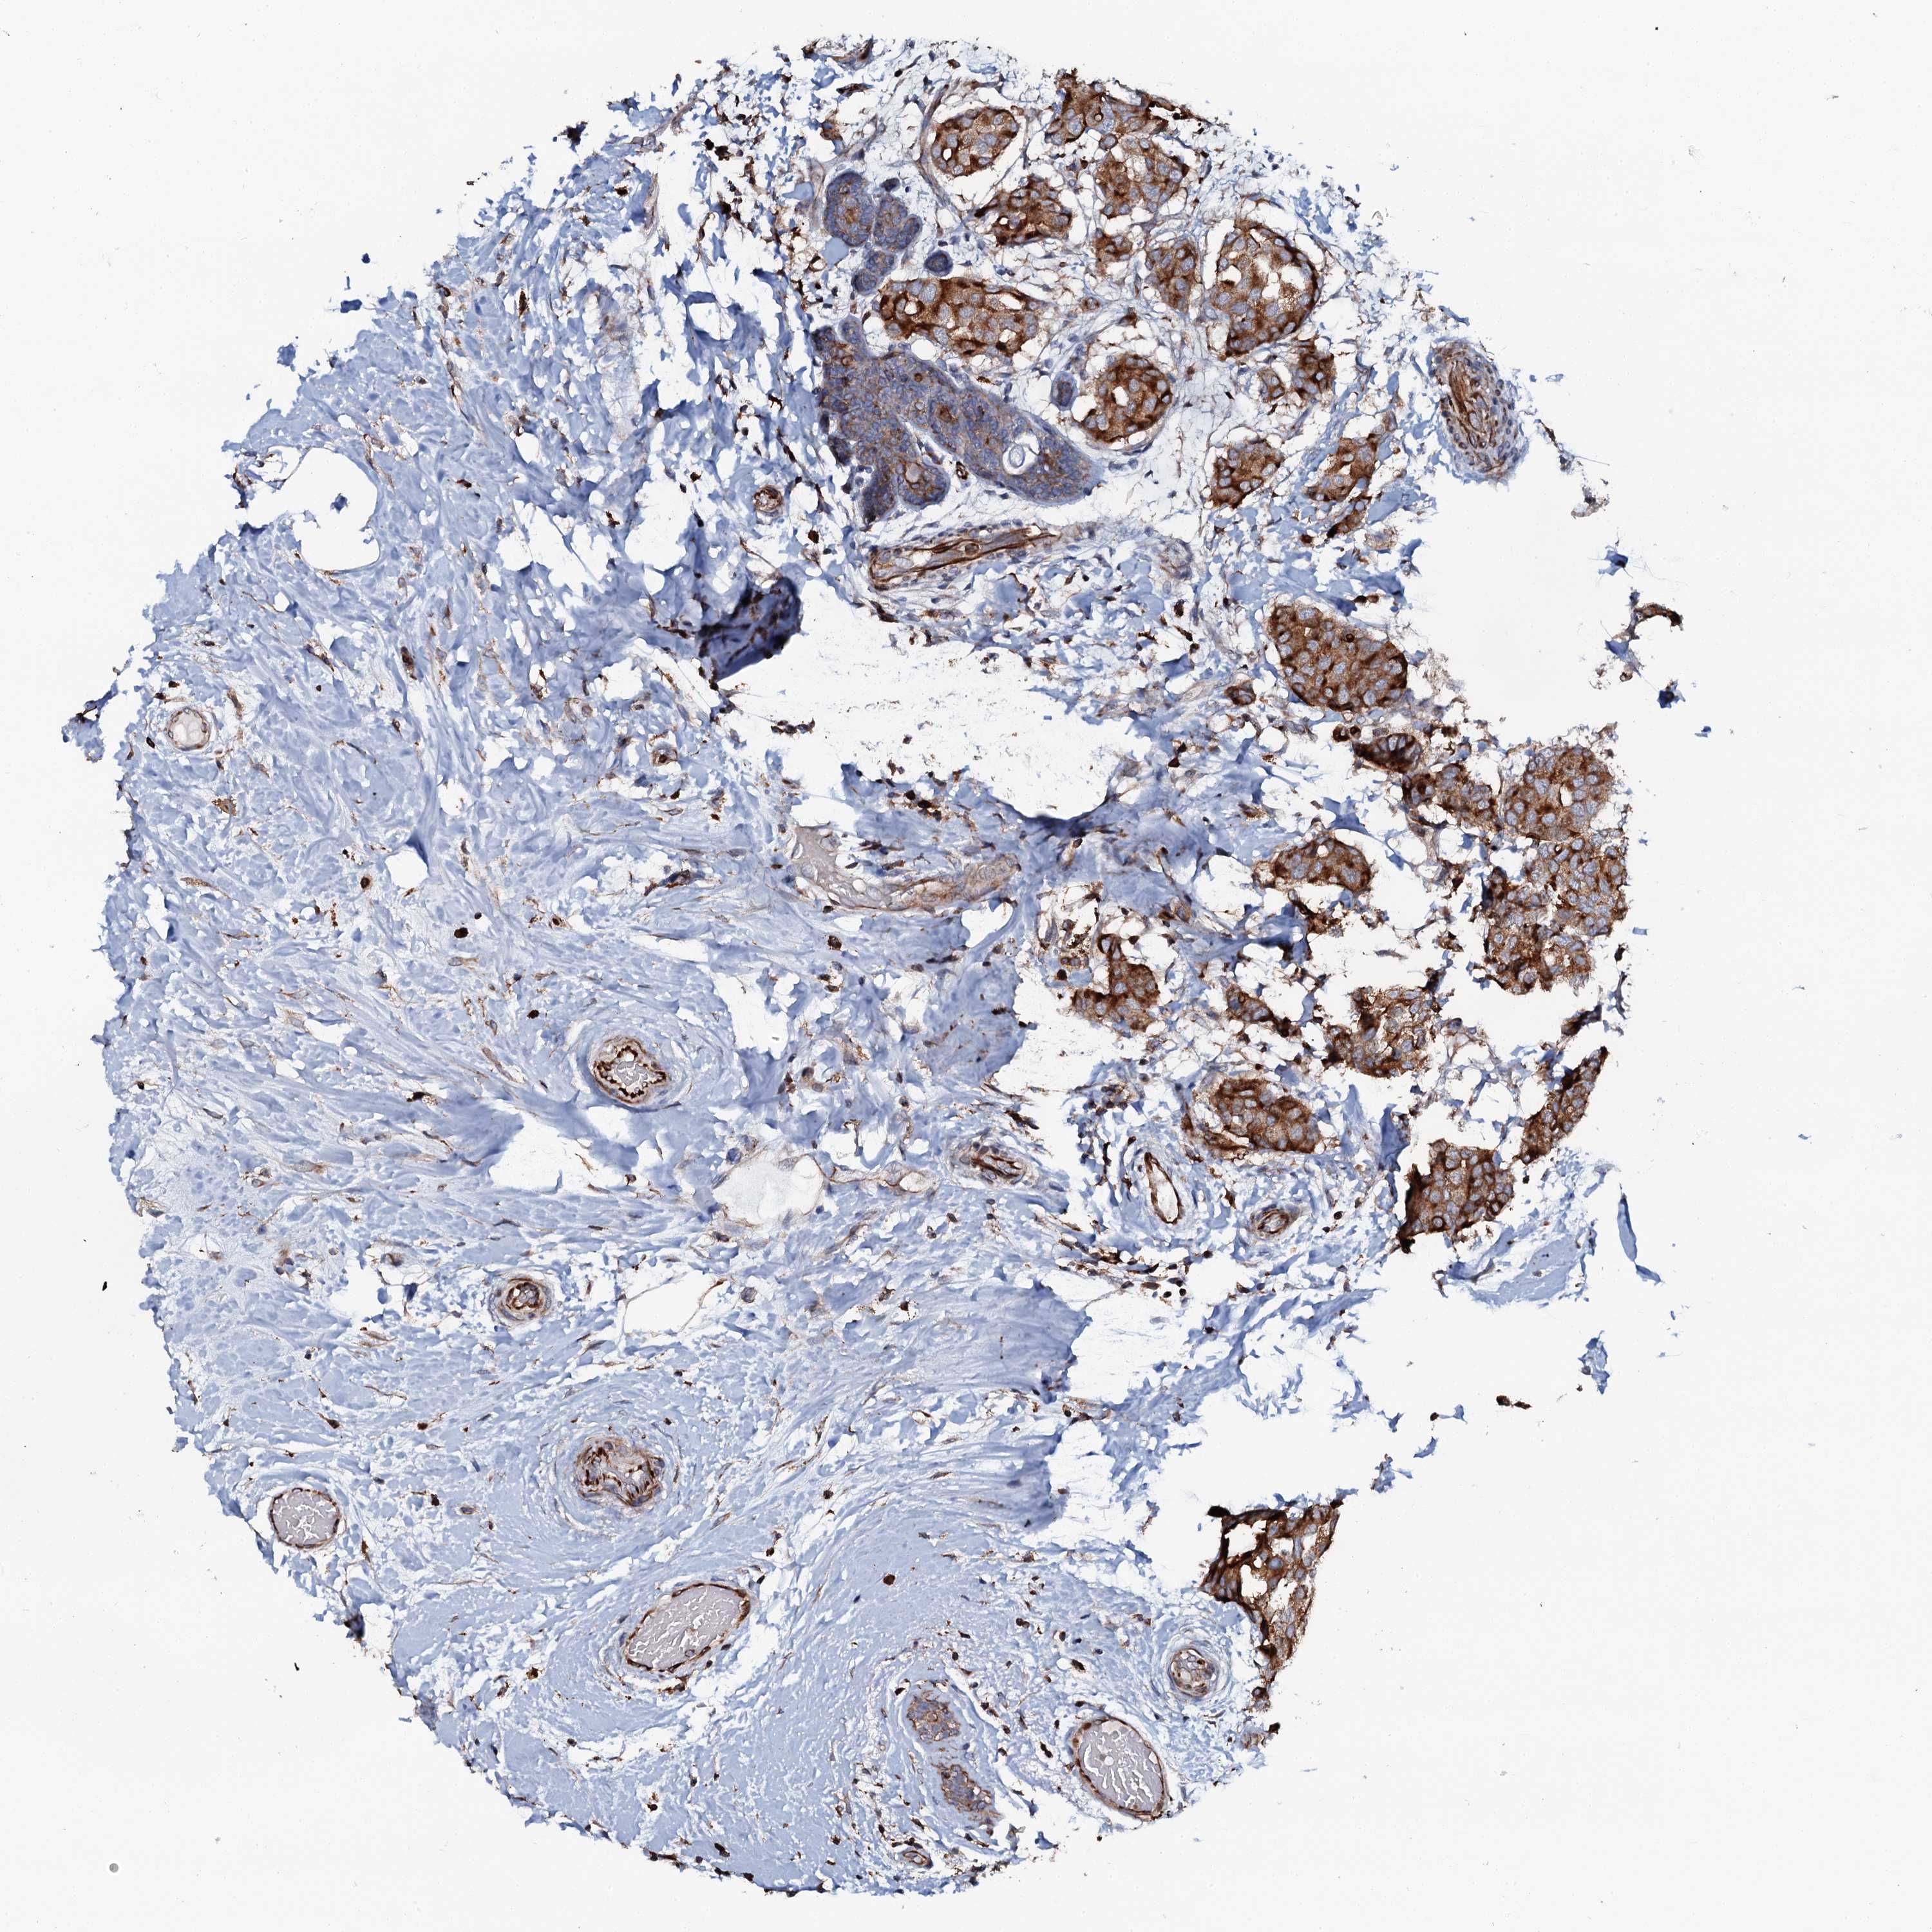

BRCA TCGA BRCA VALIDATION PROTEIN EXPRESSION